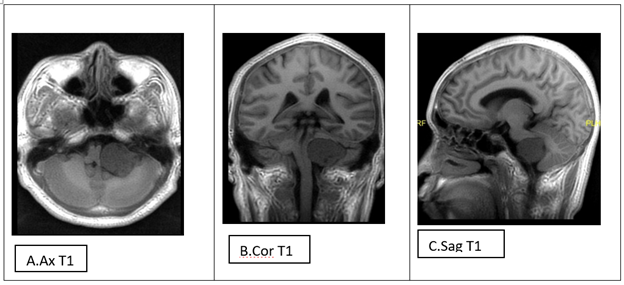

Bệnh nhân nam 41 tuổi tiền sử khỏe mạnh, đến khám với triệu chứng đau đầu vùng chẩm và thỉnh thoảng bị giảm thị lực khoảng vài tuần trước khi vào viện. Hình ảnh cộng hưởng từ sọ não trước và sau tiêm đối Gadolinium tĩnh mạch cho thấy khối giới hạn rõ, bờ khá đều, kích thước # 35x32x29mm, giảm nhẹ tín hiệu không đồng nhất trên T1, tăng nhẹ trên T2, FLAIR, SWAN, 3D CUBE, không hạn chế khuếch tán, ngấm thuốc đối quang từ mạnh không đồng nhất sau tiêm. choán chỗ ở góc cầu tiểu não trái (Hình 1.A-I). Khối chèn đẩy hành não và não thất IV sang phải (Hình 1A, B), đẩy dây thần kinh tiền đình (dây VIII) trái lên trên ra trước (1.A,D,G) và đẩy bán cầu tiểu não trái lên trên, gây phù cuống tiểu não trên trái (1.C,E). Không thấy giãn hệ thống não thất hay não úng thủy. Không có khối bất thường khác. Bệnh nhân được chẩn đoán u góc cầu tiểu não trái, khả năng u bao dây thần kinh (Schwannoma) VIII.

Hình 1. Hình ảnh khối giới hạn rõ, bờ khá đều, giảm nhẹ tín hiệu không đồng nhất trên T1 (A), tăng nhẹ trên T2(D), FLAIR(E), SWAN (F), 3D CUBE (G), không hạn chế khuếch tán(H), ngấm thuốc đối quang từ mạnh không đồng nhất sau tiêm(I) ở góc cầu tiểu não trái. Khối chèn đẩy hành não và não thất IV sang phải (Hình 1A, B), đẩy dây thần kinh tiền đình (dây VIII) trái lên trên ra trước (1.A, D, G) và đẩy bán cầu tiểu não trái lên trên, gây phù cuống tiểu não trên trái (1.C,E)

U nhú đám rối mạch mạc là loại u lành tính xuất phát từ lá thượng bì thần kinh lót màng não thất, do đó vị trí u thường gặp ở đám rối mạch mạc não thất bên (ở trẻ em) và não thất IV (ở người lớn). Vị trí u nhú đám rối mạch mạc ngoài não thất là rất hiếm gặp, kể cả ở trẻ em lẫn người lớn, bao gồm vị trí trên yên, trong nhu mô não, hố sau, bể đáy, tủy sống và vùng cùng cụt[4,8]. Trong 10 năm từ 2002-2015, số ca u nhú đám rối mạch mạc vị trí góc cầu tiểu não tra cứu được là 1 ca trong tổng số 8 báo cáo u nhú đám rối mạch mạc gặp ở các vị trí bất thường [8] và có 5 báo cáo nhắc đến trong các nghiên cứu bệnh nhân từ 3 tuần tuổi – 62 tuổi từ năm 2005 đến 2015[8], đặc biệt có 5 ca vị trí góc cầu tiểu não trong seri 10 ca bệnh nhân u nhú đám rối mạch mạc ngoài não thất[14]. Về mặt hình ảnh học, khối giới hạn rõ, đa thùy, tăng nhẹ tỷ trọng tự nhiên trên hình ảnh cắt lớp vi tính, giảm tín hiệu không đồng nhất trên T1, tăng không đồng nhất trên T2, FLAIR, SWAN, 3D CUBE, không hạn chế khuếch tán, ngấm thuốc mạnh sau tiêm đối quang từ tĩnh mạch. Đặc điểm hình ảnh như vậy chồng lấp khá nhiều với đặc điểm hình ảnh của các khối u vùng góc cầu tiểu não như u bao dây VIII, u màng não, u dưới màng nội tủy. Do đó cần cẩn trọng đưa ra chẩn đoán phân biệt khi nghi ngờ u nhú đám rối mạch mạc để tránh chẩn đoán nhầm. U dây thần kinh là loại thường gặp nhất ở góc cầu tiểu não, thương gặp với hình ảnh giảm tín hiệu trên T1, hoại tử, tạo nang trong u. Dấu hiệu gợi ý u màng não bao gồm khối hình bầu dục, đáy màng cứng rộng với dấu đuôi màng não

Với u đám rối mạch mạc điển hình, chẩn đoán hình ảnh được chỉ định ở bệnh nhân có triệu chứng lâm sàng nghi ngờ tăng áp lực nội sọ/não úng thủy hoặc u nội sọ[5,7]. Nếu thóp chưa đóng, siêu âm qua thóp có thể phát hiện khối hồi âm bên trong não thất. Hình ảnh CT có thể phát hiện khối đồng/tăng nhẹ tỷ trọng trong não thất kèm giãn não thất/não úng thủy, 25% khối u có thể có vôi hóa lấm tấm kèm giãn động mạch đám rối mạch mạc. Hình ảnh MRI cho thấy khối giới hạn rõ, đều, đa thùy giảm tín hiệu trên T1, tăng trên T2, có thể có flowvoid và giàu mạch, ngấm thuốc mạnh sau tiêm.